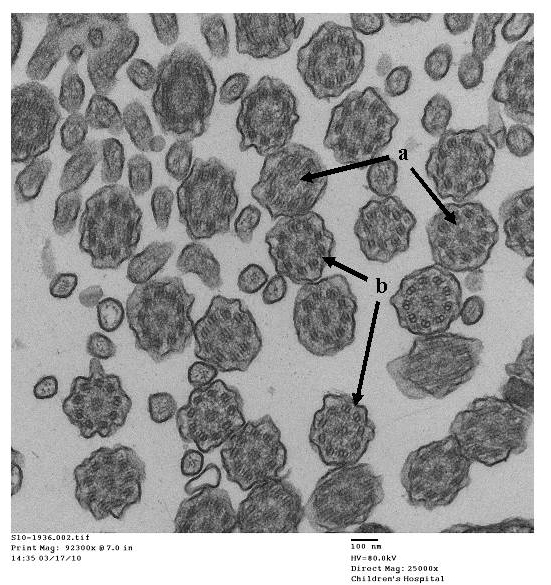

- Papon JF: A 20-year experience of electron microscopy in the diagnosis of primary ciliary dyskinesia. European Respiratory Journal 2010;35(5):1057-1063.